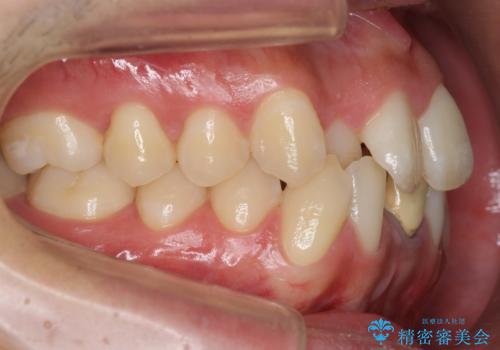

- 前歯のガタガタを主訴に来院。

下の前歯は一本保険治療での被せ物になっており、変色していました。

のプランを提案し、神経のない前歯を抜く選択をされました。

下の前歯が3本になり奇数になることで、上下の真ん中は一致しませんが、そこまで目立たないと思います。

ブラックトライアングルも少なめで、短期間でしっかり並びました。

上の前歯のガタガタも、わずかに歯を削って並べていますので、出っ歯になったりしないようにしています。